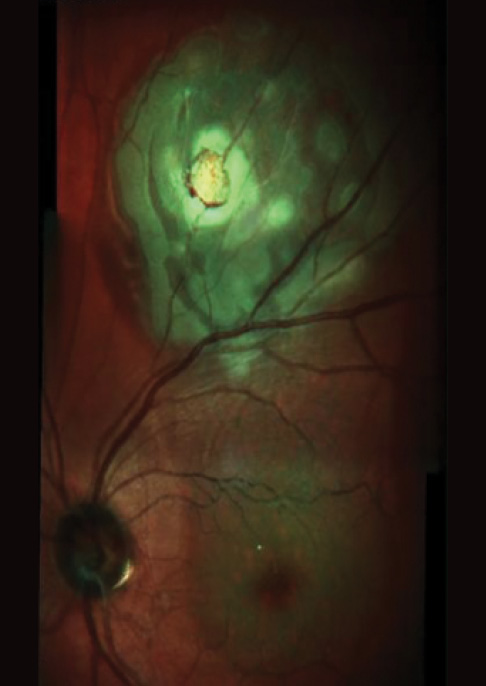

Figure 2. Spectral-domain OCT scan 1 day after transvitreal biopsy.

Figure 3. Multicolor montage of fine needle aspiration biopsy site 1 day postoperative.

Treatment of small uveal malignant melanoma (Figure 1) is controversial. GEP allows prognostication for small uveal melanomas with minimal surgical risk (Figures 2 and 3). This technology affords clinicians the opportunity to treat earlier in the disease process, thereby minimizing the likelihood of metastatic spread.